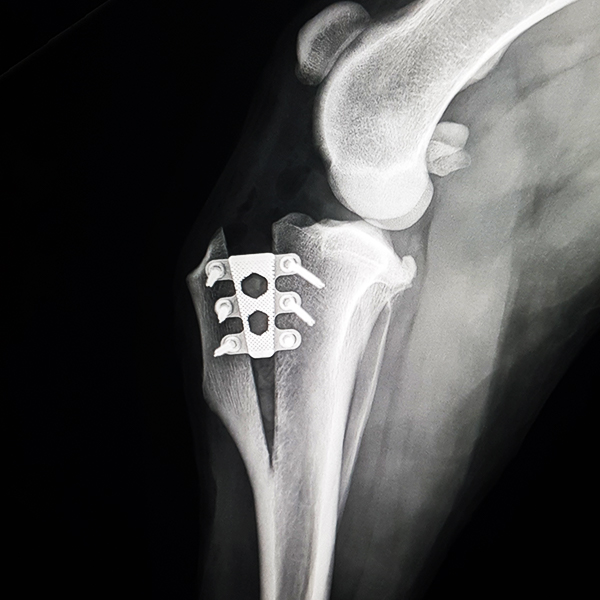

Case Overview In November 2025, Skeeter, a 14-week-old Doodle puppy weighing ...

Pioneering Small PatientOrthopedics with the 1.5 mmLeiLOX TPLO Swing Titanium Plate ...